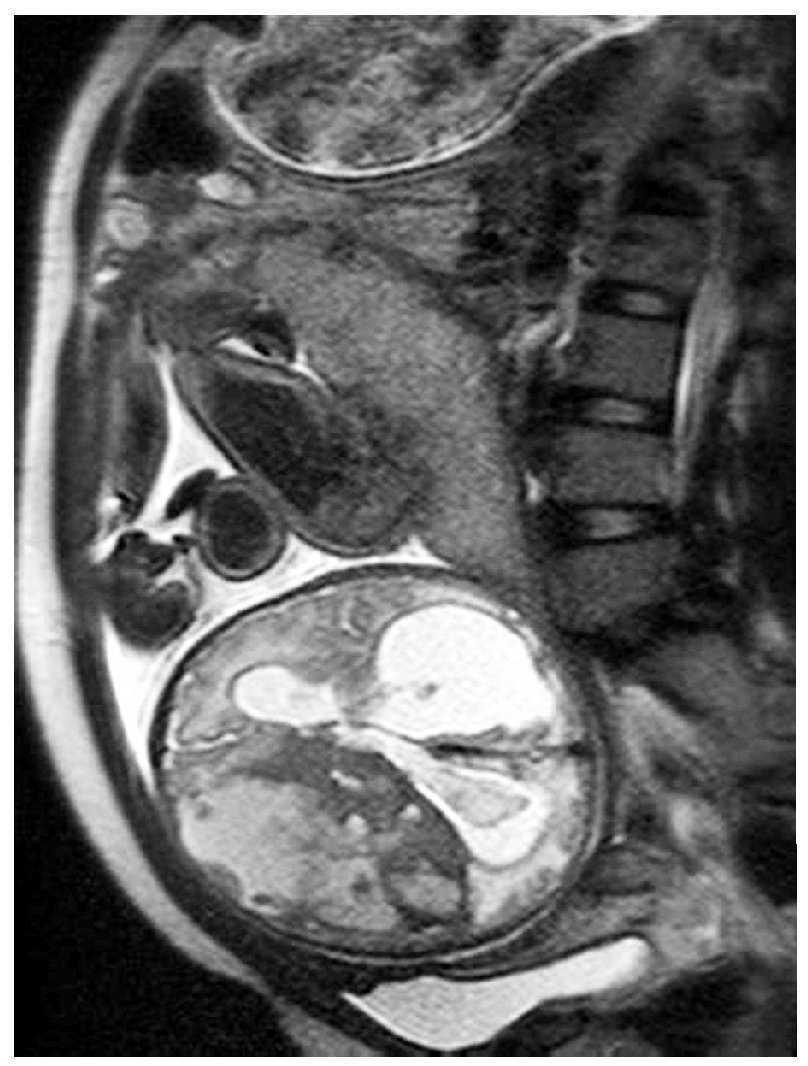

Gestante en el séptimo mes del embarazo. En ecografía de control se detecta hidrocefalia.

Fig. 4.